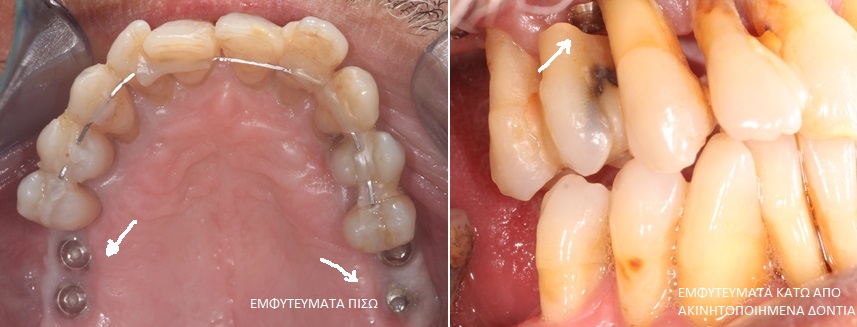

Βλέπουμε στην φωτογραφία που ακολουθεί αριστερά, τα εμφυτεύματα στην θέση των πίσω δοντιών ενώ δεξιά βλέπουμε εμφυτεύματα που τοποθετήθηκαν μετά την εξαγωγή των δοντιών κάτω από ακινητοποιημένα με σύρμα δόντια.